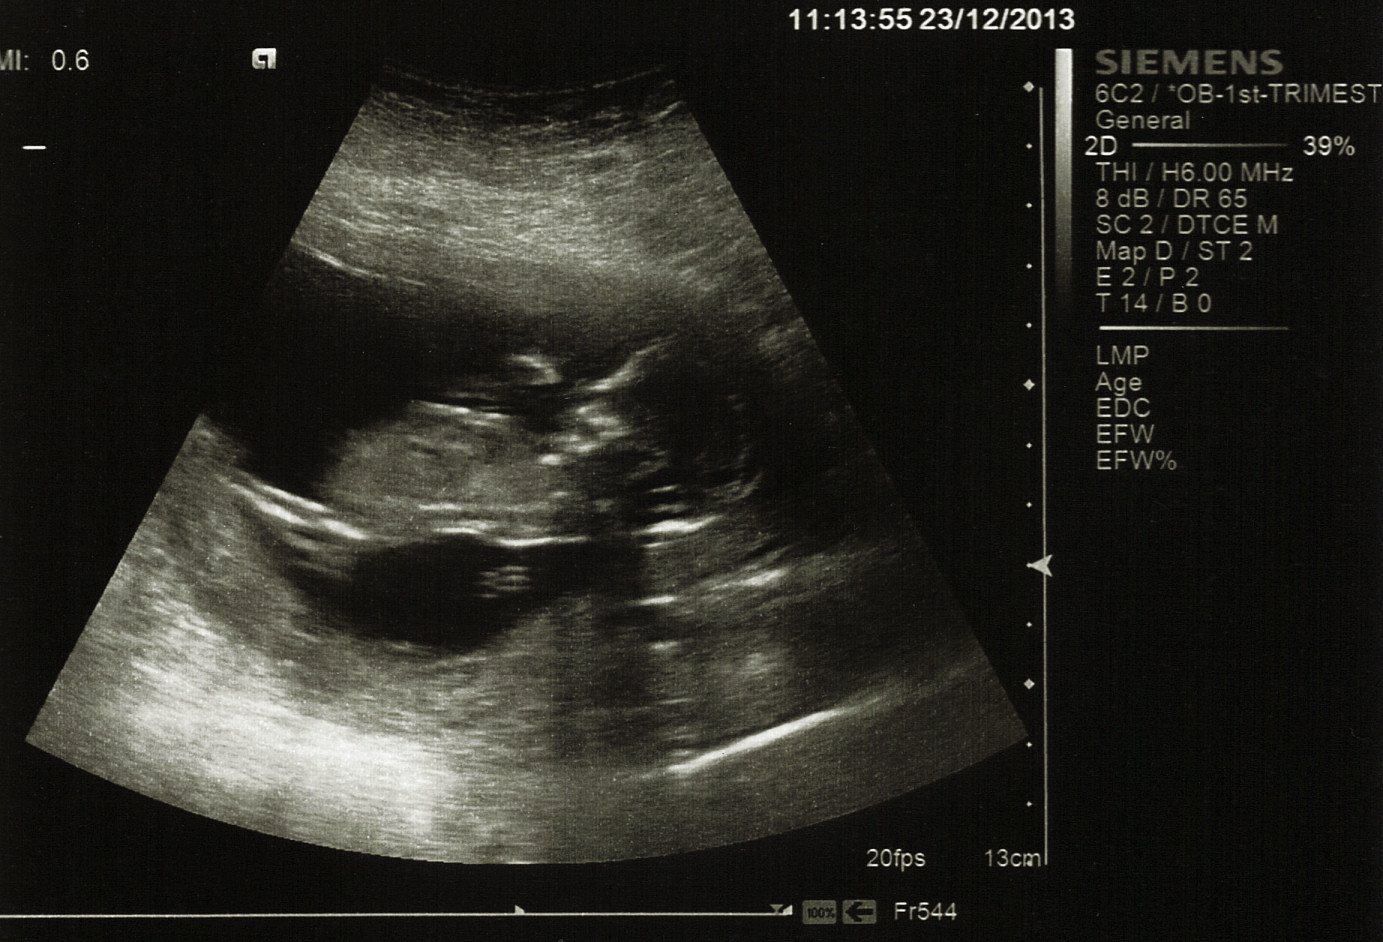

Also for those who know their stuff: there are lines underneath baby's back in the last picture that DH and I are trying to figure out what they are. Any clues?

Attachment 15866